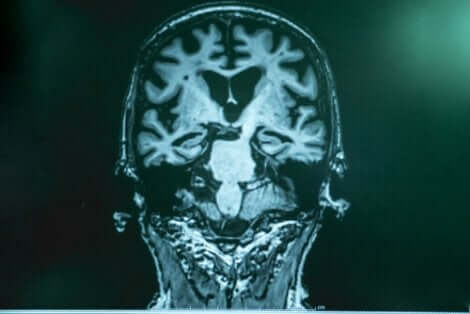

로페라 박사는 알츠하이머병과 함께 뇌에 일종의 ‘쓰레기’가 축적된다고 설명한다.

이러한 쓰레기는 아밀로이드라는 단백질로 구성되어 있다. 아밀로이드 파편이 하나로 뭉쳐지면서 일종의 ‘접착제’를 형성한다. 이는 뉴런에 달라붙어 뇌에 여러 기능 부전을 일으킨다.

‘쓰레기’의 다른 부분은 뉴런을 휘감아 가둔 뒤 죽이는 타우이다. 타우는 더 해롭다.

보스턴에서 세심한 연구를 한 끝에, 전문가들은 환자의 뇌가 다른 사례보다 훨씬 더 많은 아밀로이드로 가득 차 있다는 사실을 발견했다. 하지만 타우는 거의 없었다.

이 연구를 통해, 특정 환자에서 또 다른 돌연변이가 타우 생성을 억제했으며 이로 인해 질병의 진행이 지연되었다는 것을 확인할 수 있다.